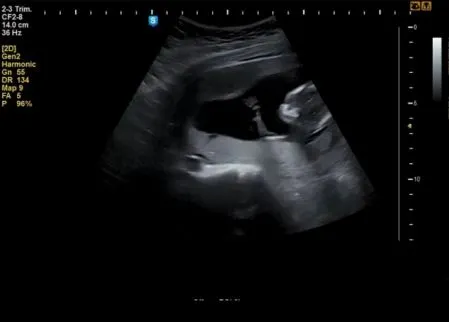

[육아일기] 딸일까, 아들일까

[육아일기] 딸일까, 아들일까?

햇살이 네가 딸인지, 아들인지 말이야.

우리 햇살이가 딸이라면 어떨까?

아니 아들이라면?

캡처.JPG 5월에, 교회 사람들에게 OX퀴즈를 낼 거야. "아들이면 O, 딸이면 X로 가라고."